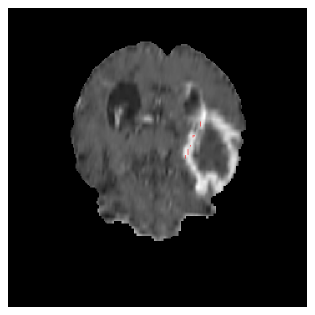

Appendix A Qualitative results

Figures 4 and 5 present the segmentation results for a patient from the BRATS dataset, visualized on a randomly selected slice. Figure 4 illustrates how tumor segmentation evolves over multiple episodes in S1 across different approaches including cumulative, naive, our approach, and the best buffer-free strategy (SI, =2). The cumulative approach, which trains on all encountered datasets together, maintains segmentation consistency across episodes but introduces significant amounts of false positives, particularly in the upper left area of the brain images. These misclassifications highlight its inability to generalize well across datasets despite access to all previous data. The naive approach, which learns sequentially without any continual learning strategy, suffers from severe catastrophic forgetting. While it initially segments well, performance deteriorates over episodes, leading to a near-complete loss of segmentation capability by the final episode. The SI (=2) approach, a regularization-based buffer-free CL strategy, performs reasonably well in early episodes but shows a significant performance decline over time. By the last episode, much of the tumor was no longer segmented, indicating difficulty in retaining prior knowledge. In contrast, our proposed approach initially produces more false positives but progressively refines its segmentation. By the final episode, it accurately retains the tumor region while minimizing misclassifications, demonstrating strong knowledge retention and adaptability across episodes. This suggests that our approach effectively mitigates catastrophic forgetting while maintaining segmentation performance over sequential learning.